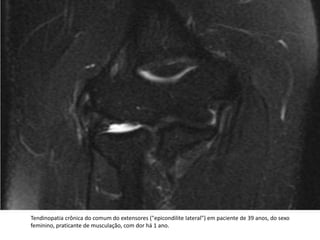

DIAGNÓSTICORM do cotovelo, no plano coronal, em três sequências diferentes.Espessamento heterogêneo da porção proximal do tendão extensor comum, podendo haver pequenas rupturas parciais. Edema de partes moles superficiais adjacentes (setas).

Tendinopatia crônica do comum do extensores ("epicondilite lateral") em paciente de 39 anos, do sexo feminino, praticante de musculação, com dor há 1 ano.